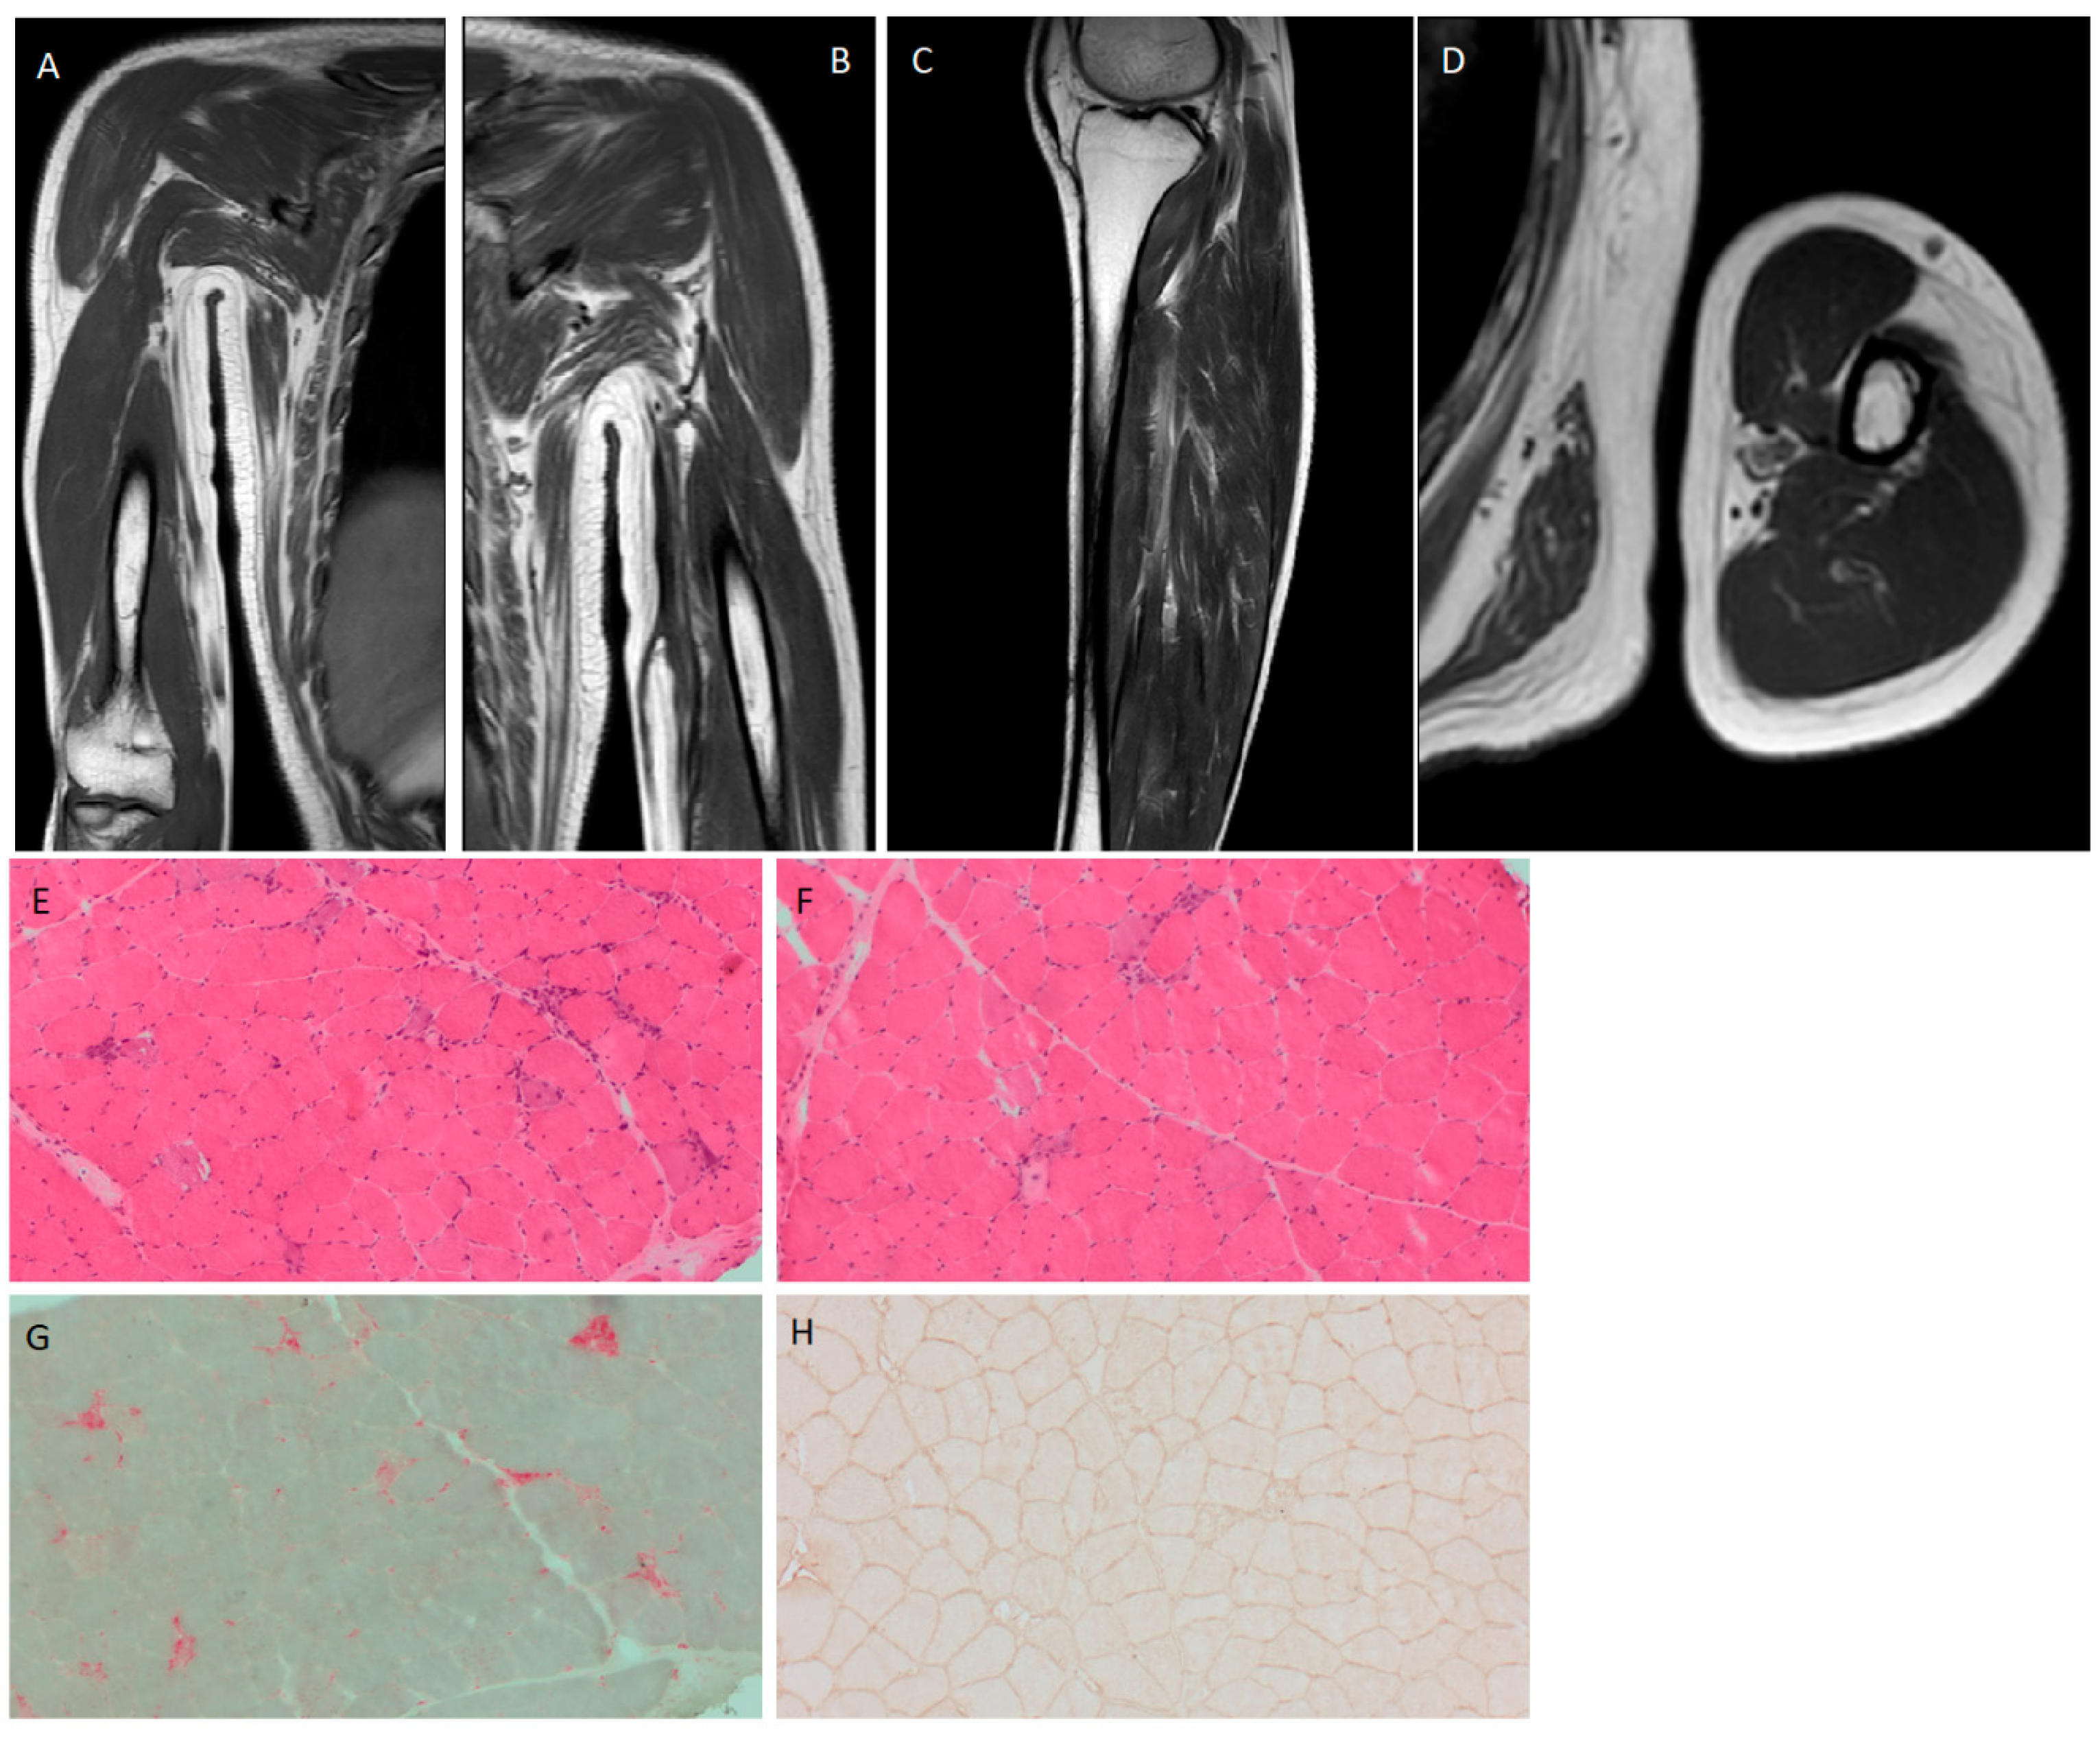

2. Case Presentation